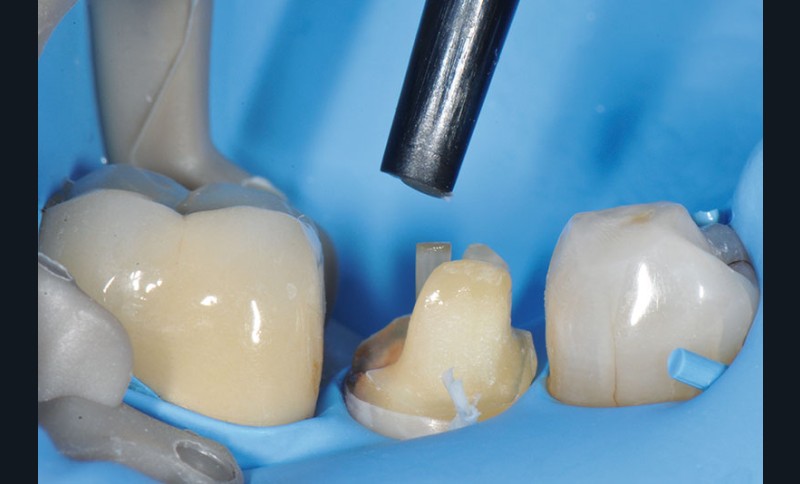

7, 8, 9. L’obturation canalaire à la gutta percha est partiellement éliminée avec le foret universel et le canal radiculaire est mis en forme avec le foret de calibrage 3M™ RelyX™ Fiber Post de 1,1 mm de diamètre. L’élimination totale de la gutta percha sur la longueur désirée est vérifiée à l’aide d’une radiographie rétro-alvéolaire. Un insert à ultrason est utilisé, son action mécanique permettant de finir de nettoyer le système canalaire et d’éliminer les résidus de ciment endodontique pouvant encore être présents.